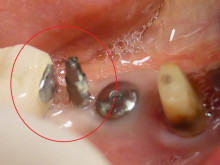

赤丸が、仮のインプラント(MTI)です。

本当のインプラントの横に入れてあります。

本当のインプラントが骨と結合する2か月間 使えればいいのです。